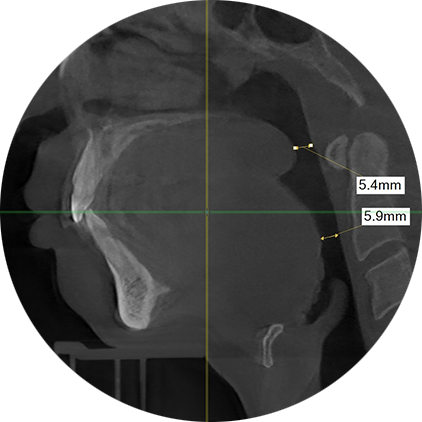

32세 남자, 코골이 수술 이후 재발되어 내원하셨습니다.

이전 수술 효과는 미미했으며 이전 목젖 절제 및 연구개 성형술로 연구개가 짧아져 있으나 여전히 5mm미만으로 좁은 기도입니다.

수면다원검사 이후 중증 수면무호흡증으로 진단 되었습니다.

수술 전

연구개 뒤 4.94mm, 혀 뒤 7.84mm로 기도가 전반적으로 좁아져 있습니다. 원래 무턱으로 코골이·수면무호흡증이 심할 수 있는 뼈 구조이며 무턱성형술을 받아서 턱 아래가 앞으로 나와 있습니다.

수술 후 3개월

연구개 뒤 7.06mm, 혀 뒤 11.55~14.06mm로

정상에 가까운 기도(숨구멍)모양으로 바뀌어져 있습니다.